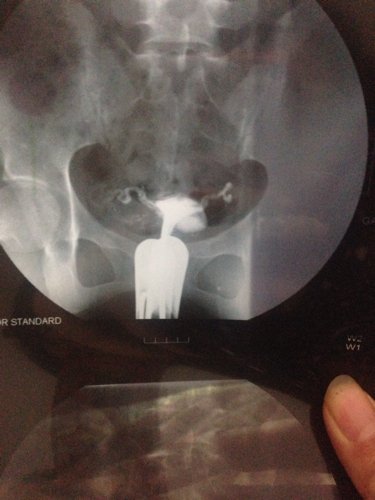

没有刻意避孕也没有备孕,每周一次性生活。两年没有一次意外怀孕,现在想要宝宝,老公检查双侧精索静脉曲张,前列腺质地欠均匀,左侧鞒膜腔积液,精液及精子质量分析显示精子密度6.38%,a级精子17.24b级10.34c级37.93d级34.48。我排卵正常,无霉菌滴虫及细菌性阴道病,子宫大小5.2·3.5·4.1,形态规整,肌层分布均匀,子宫内膜线居中,子宫及双侧附件区未见异常,盆腔未见积液。输卵管造影显示子宫呈倒三角形,轮廓光整,双侧输卵管显影良好,形态未见明显异常,均见少量造影剂进入盆腔,弥散欠佳。双侧输卵管欠通畅,但是治疗医生说片子上面看是通的。现在很着急,不知道下一步怎么办…求医生指导。